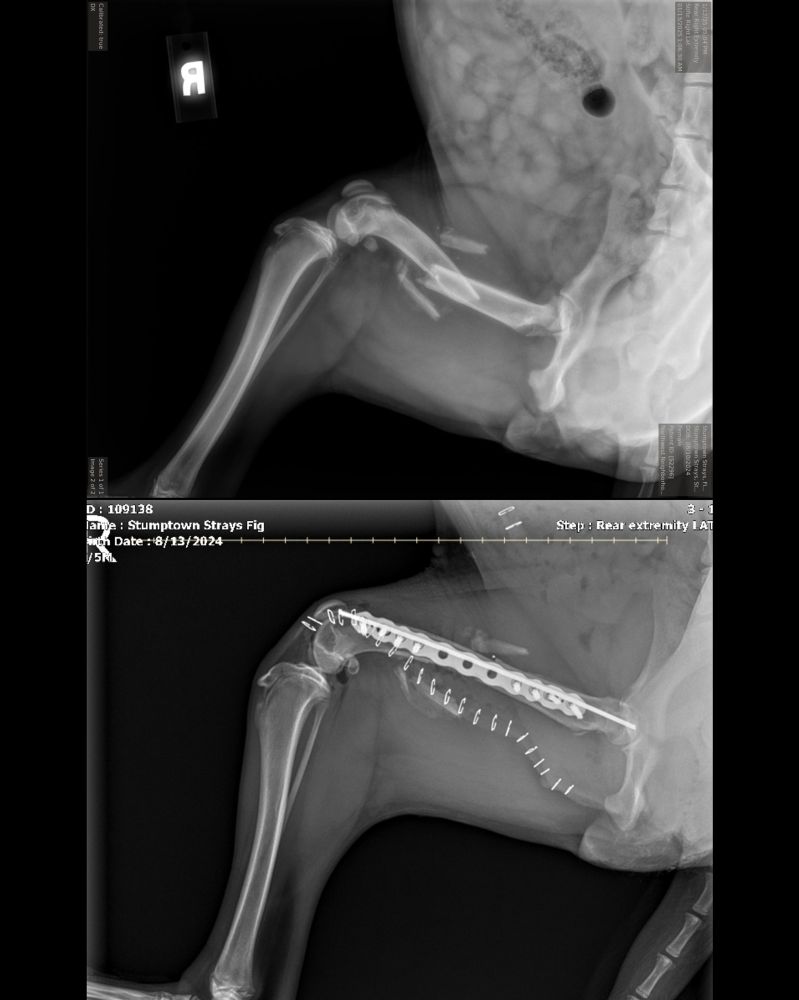

This is Fig. She was found as a stray who had been hit by a car. She needed surgery and wound up with a rod, a plate, 8 screws, and 23 staples in her leg. Thanks to your support of our merch, @15outof10.org was able to cover her $8,000 surgery. She has since fully healed and found a forever home ❤️‍🩹